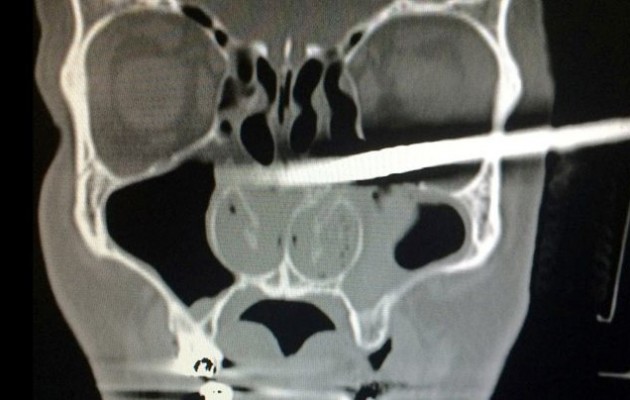

Άνδρας πήγε με στο νοσοκομείο με ένα κομμάτι ξύλο καρφωμένο στο κεφάλι του! Όσο απίστευτο και αν ακούγεται ο Καμίλ Ποντουίνσι (Kamil Podwinski) την ώρα που έκανε κάποια μερεμέτια στο σπίτι του, γλίστρησε να πέφτωντας καρφώθηκε στο πρόσωπό του ένα μεγάλο κομμάτι ξύλο, το οποίο μάλιστα διαπέρασε το κρανίο του και βγήκε από την πίσω πλευρά του κεφαλιού του.

Όπως αναφέρει το Central European News, το ξύλο τρύπησε τον Kamil κάτω από το μάτι του και βγήκε από τον αυχένα του.

Οι γιατροί σάστισαν όταν αντίκρυσαν το αποτρόπαιο θέαμα, μη γνωρίζοντας αρχικά τι ακριβώς να κάνουν για να αφαιρέσουν το ξύλο χωρίς να προκαλέσουν περαιτέρω βλάβες στον 40χρονο που υπέφερε από τον πόνο.

Ωστόσο, λίγες ώρες μετά κατάφεραν να βγάλουν το αντικείμενο, χωρίς να πάθει τίποτα ο Kamil.

«Καταφέραμε να αφαιρέσουν το ξύλο και πλέον ο άνδρας αναρρώνει στο νοσοκομείο. Χρειάζεται παρακολούθηση αλλά είναι καλά» ανέφεραν οι θεράποντες γιατροί.